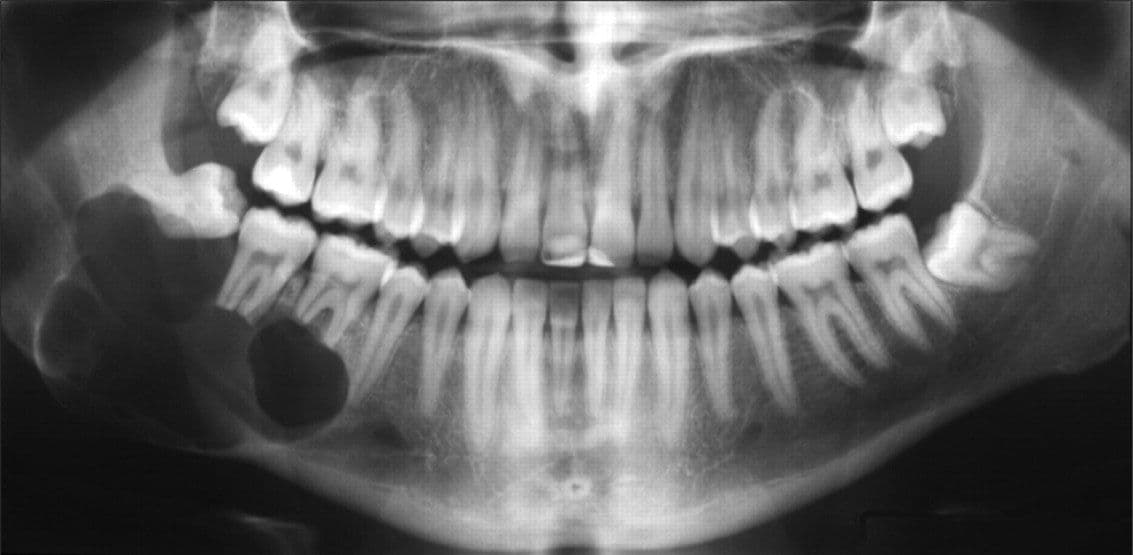

– Quan sát trên hình ảnh chụp XQuang thấy mất răng vĩnh viễn. Một số trường hợp khác nang răng liên quan trực tiếp tới các răng ngầm, răng khôn.

Hình ảnh chụp XQuang hàm có nang răng